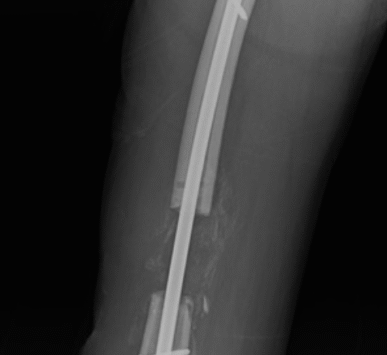

Entre sus áreas de especialización, se encuentran el tratamiento de fracturas complejas, la cirugía de pelvis y acetábulo mínimamente invasiva y la reconstrucción ósea con fijadores circulares para el tratamiento de pseudoartrosis e infecciones.

Ocurre cuando una fractura no sana correctamente o tarda más de lo esperado en curar.